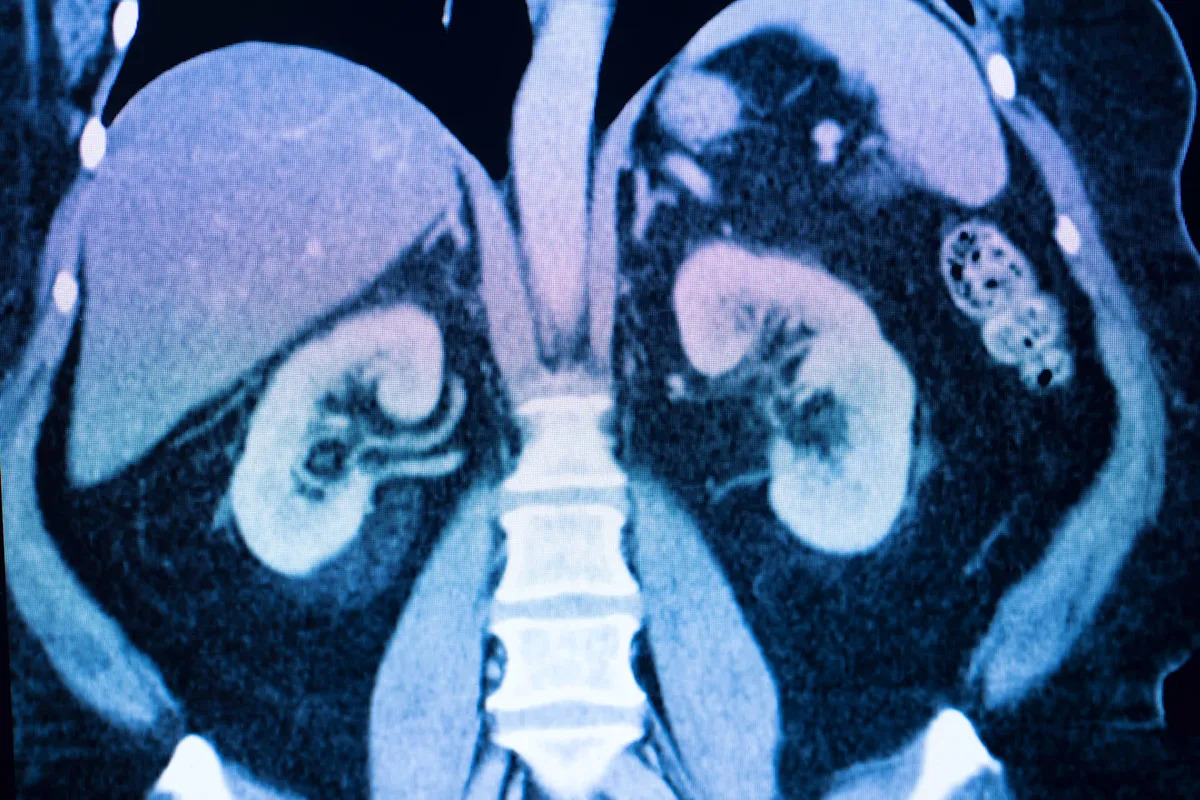

À medida que mais resíduos plásticos são lançados no meio ambiente, os microplásticos presentes na água potável e nos alimentos são ingeridos pelos seres humanos, causando danos aos órgãos internos após serem absorvidos pelo sistema digestivo. Isso ocorre principalmente nos rins, conforme encontrado em um estudo publicado pela Communications Biology.

O estudo descobriu que os microplásticos – minúsculas partículas de plástico com menos de 5 milímetros de comprimento – são os principais transportadores do poluente ambiental Benzo(a)pireno para o corpo. As vias específicas não são totalmente compreendidas, mas há evidências de que o BaP é absorvido principalmente através dos intestinos após a ingestão oral, o que representa riscos para a saúde.

O estudo revisado por pares descobriu que a água engarrafada é a principal fonte de microplásticos, causando danos à parede intestinal e aos rins e causando inflamação sistêmica.